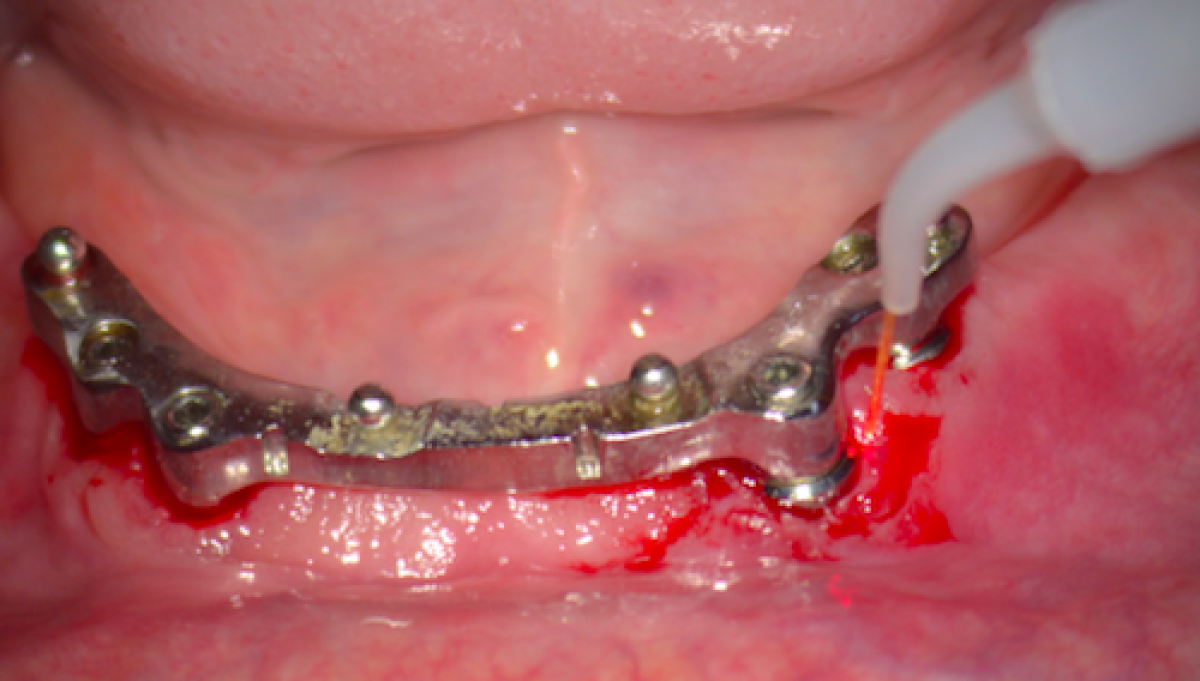

OBJECTIVES. The aim of this work is to identify the effectiveness and criticality of laser use in dentistry in the light of medico-legal evaluations.

MATERIALS AND METHODS. We analyze the characteristics of dental lasers, scientific evidence and some cases of litigation. We want to stimulate a conscious use of the laser and reduce unwanted effects. The negative side effects are the cause of litigation and disputes frequently.

RESULTS. The use of laser technology in medicine in dentistry is a reality that will find more and more applications. This use presupposes a knowledge of the fundamental principles of physics, mechanics and human tissues, as well as of the reference standards for the protection of patients and operators. The prevention of unwanted events and litigation passes from a profound knowledge of the subject

Although the discovery of lasers and research into their applicability for dental use began in the 1960s, it was not until 1985 that the first documented use of a laser in periodontal surgery was...